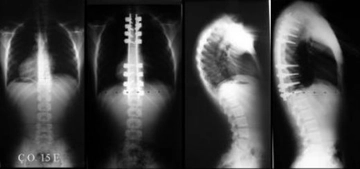

Dorsal Kifoz Nedir?Dorsal kifoz, omurganın üst kısmında, yani torasik bölgede meydana gelen bir eğrilik türüdür. Normalde omurgada doğal eğrilikler bulunmakla birlikte, dorsal kifozda bu eğrilik anormal bir şekilde artar ve genellikle sırtın üst kısmında bir kamburluk görünümüne neden olur. Dorsal kifoz, genellikle ergenlik döneminde veya yaşlılıkta ortaya çıkar, ancak çeşitli nedenlere bağlı olarak her yaş grubunda görülebilir. Dorsal Kifozun NedenleriDorsal kifozun birçok olası nedeni bulunmaktadır. Bu nedenler arasında:

SonuçDorsal kifoz, sırt bölgesinde anormal bir eğrilik olarak tanımlanabilir ve birçok sağlık sorununa yol açabilir. Erken teşhis ve uygun tedavi yöntemleri ile bu durumun etkileri azaltılabilir. Dorsal kifozun önlenmesi ve tedavisi için düzenli egzersiz yapmak, doğru duruş alışkanlıkları geliştirmek ve gerektiğinde profesyonel yardım almak önemlidir. Ekstra BilgilerDorsal kifoz ile ilişkili sağlık sorunlarının önlenmesi için, bireylerin günlük yaşamlarında dikkat etmeleri gereken bazı noktalar bulunmaktadır: